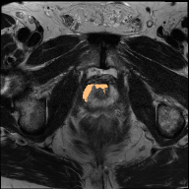

PROMISE12 Dataset: PROMISE12 dataset [18] consists of 50 transverse T2-weighted MRI scans. Following the data split in Liu et al. [19], there are 35, 5, and 10 scans for training, validation, and testing.

Some qualitative segmentation results on the three datasets are shown in Fig. 4, where we can observe that the proposed DSPIF achieves accurate segmentation results.

Results on PROMISE12 Dataset: In Tab. 3, based on MCNet baseline, the proposed method achieves 24.0% Dice and 23.78% JAC (resp., 7.86% Dice and 8.16% JAC) improvement under the setting of using 10% (resp. 20%) labeled data. Compared with state-of-the-art method BCP [3], the proposed method built on CPS [10] achieves an improvement of 3.89% (resp. 3.73%) Dice when using 10% (resp. 20%) labeled data.